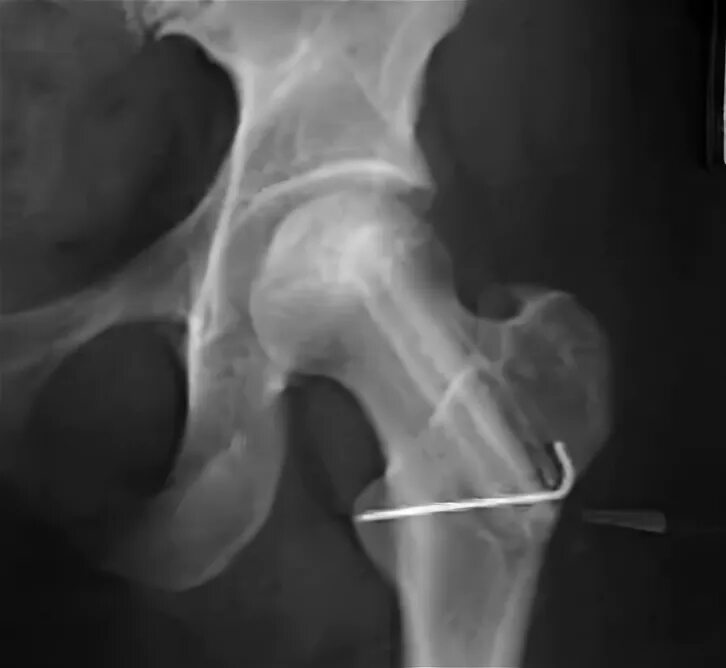

Асептический некроз тазобедренного сустава лечение без операции